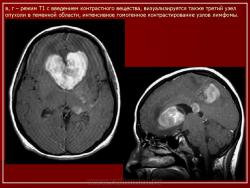

Лимфомы головного мозга.